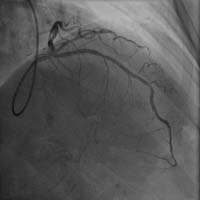

前降支近端嚴重狹窄 介入術(shù)后狹窄消失